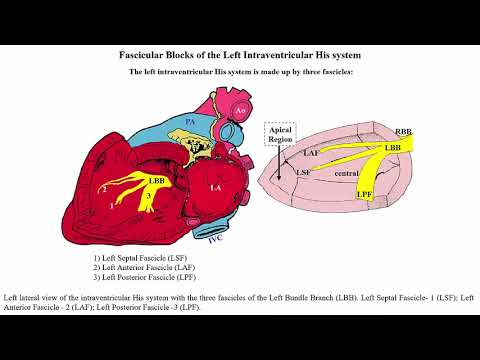

El bloqueo de las fibras medias de la rama izquierda del Haz de His. Dr. Andrés R. Perez Riera. Facultad de Medicina ABC de San Andrés. San Pablo. Brasil